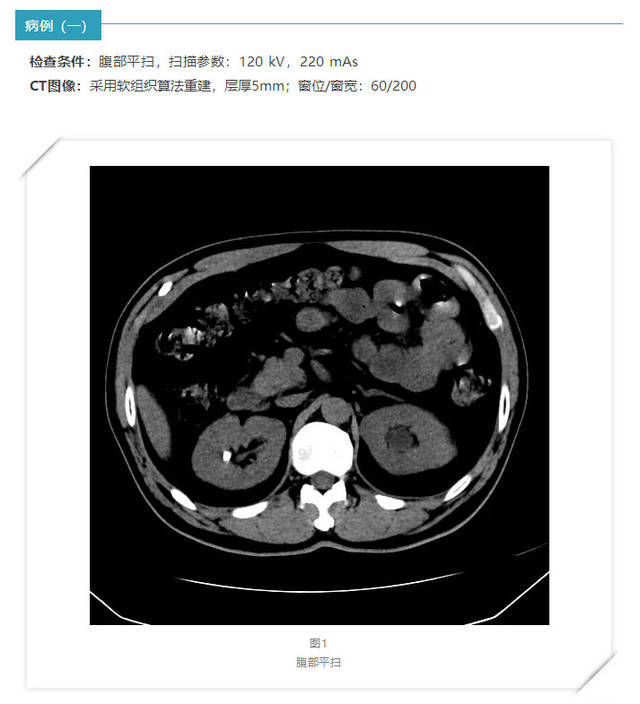

腹部螺旋ct

腹部ct扫描

腹部病变ct

上腹部ct

医学影像学腹部ct

上腹部ct平扫&增强病例断层解读

手把手教你看腹部ct

腹部ct超全断层解剖